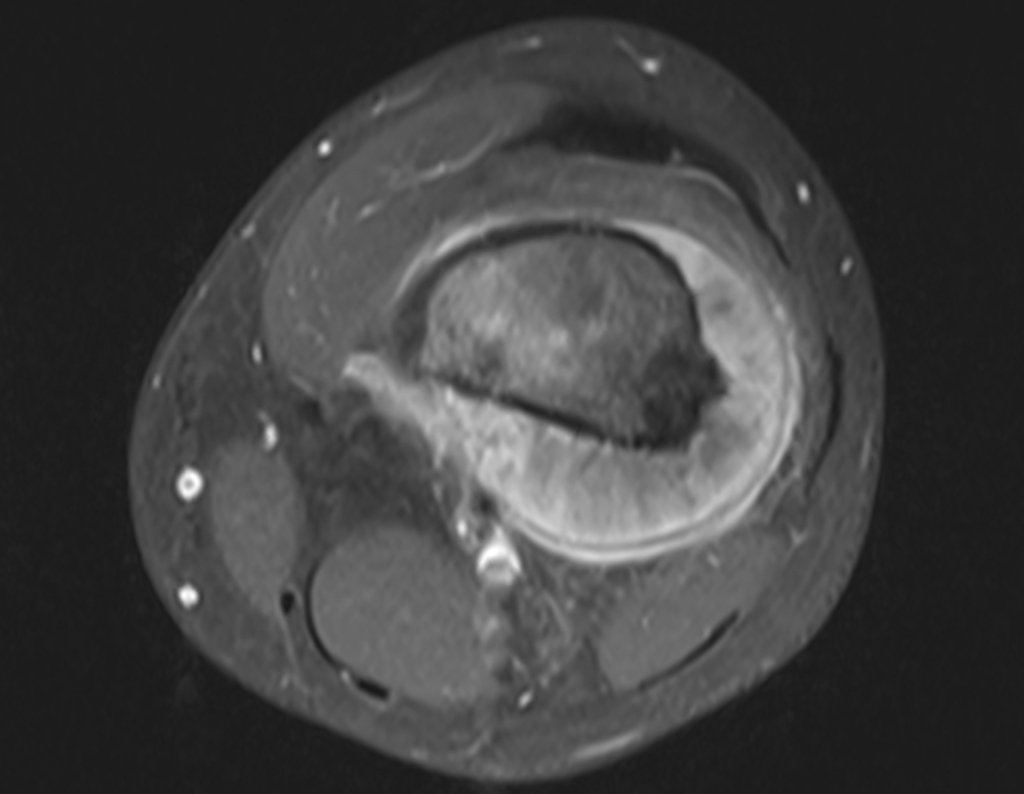

Osteosarcoma de fémur - Prótesis de rodilla no convencionales - Discrepancia de longitud - Epifisiodesis de fémur y tibia.